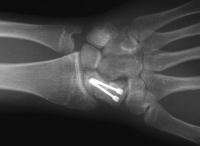

Clinical Example: Revision scaphoid nonunion with hardware removal, bone graft and two Herbert screws

This 19 year old had been treated elsewhere with an accutrac screw for a displaced scaphoid fracture. He was noncompliant with immobilization after surgery, and developed a painful nonunion.

The nonunion was reconstructed by removing the hardware, iliac bone graft and two Herbert screws placed through new paths. Cancellous bone was packed into the old screw hole.